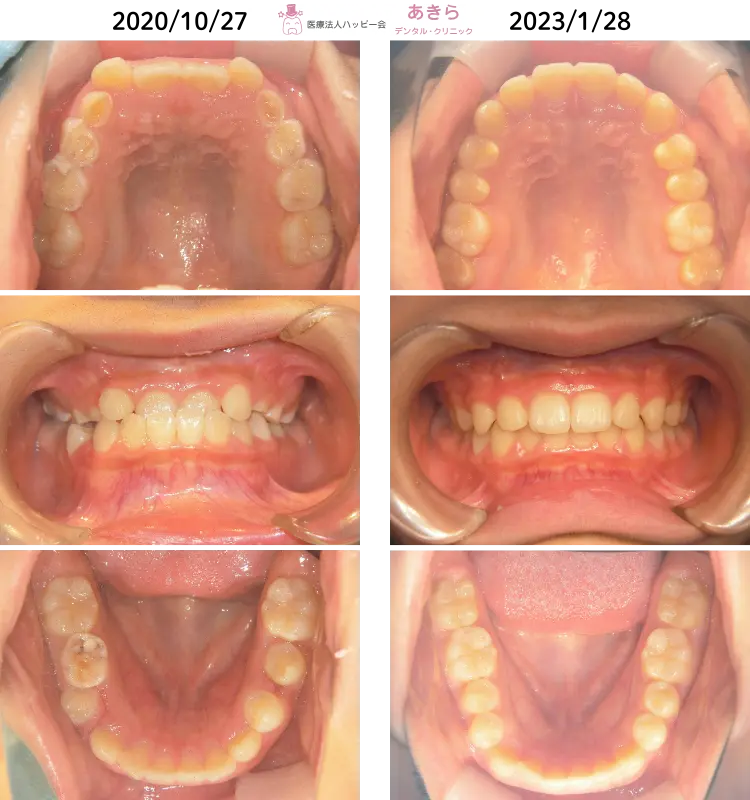

当院の症例

SH療法

SH療法-症例-No.014-左上5番の口蓋側転移位を伴なう症例

山形市の歯医者「あきらデンタル・クリニック」のSH療法の症例をご紹介します。 SH… -

SH療法-症例-No.013-右上5番の著しい口蓋側転移位を伴なう症例

SH療法-症例-No.012-外傷歯を伴う叢生(凸凹)の矯正症例

症例

予防的矯正治療(プレオルソやマウスピース型装置を主に使用)-症例-No.008

山形市の歯医者「あきらデンタル・クリニック」の予防的矯正治療(プレオルソやマ… -

SH療法-症例-No.011-下顎右側偏位を伴う「プレオルソ」を保定として使用した症例

予防的矯正治療(プレオルソやマウスピース型装置を主に使用)-症例-No.007

山形市の歯医者「あきらデンタル・クリニック」の予防的矯正治療(プレオルソやマ…